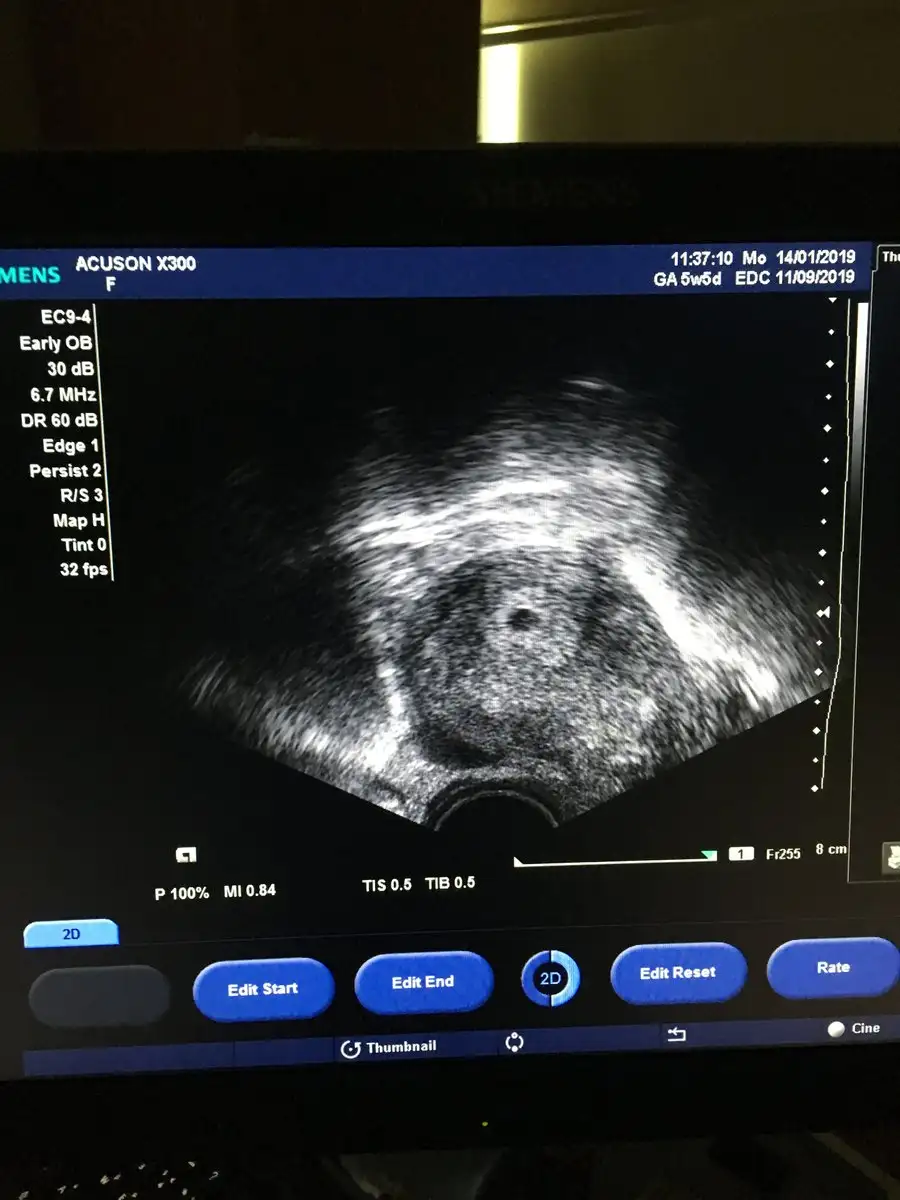

Canim merhaba benim ultrason fotograflarima da bakabilir misin cinsiyet tahmini icin merak ediyorum. 3u de vajinal ultrason 5-6-9.haftalarda

Eklentiler

• 47EE10A5-E4E3-4CF0-BC8F-6F29AAB60B03.webp

47EE10A5-E4E3-4CF0-BC8F-6F29AAB60B03.webp

49,2 KB · Görüntüleme: 92